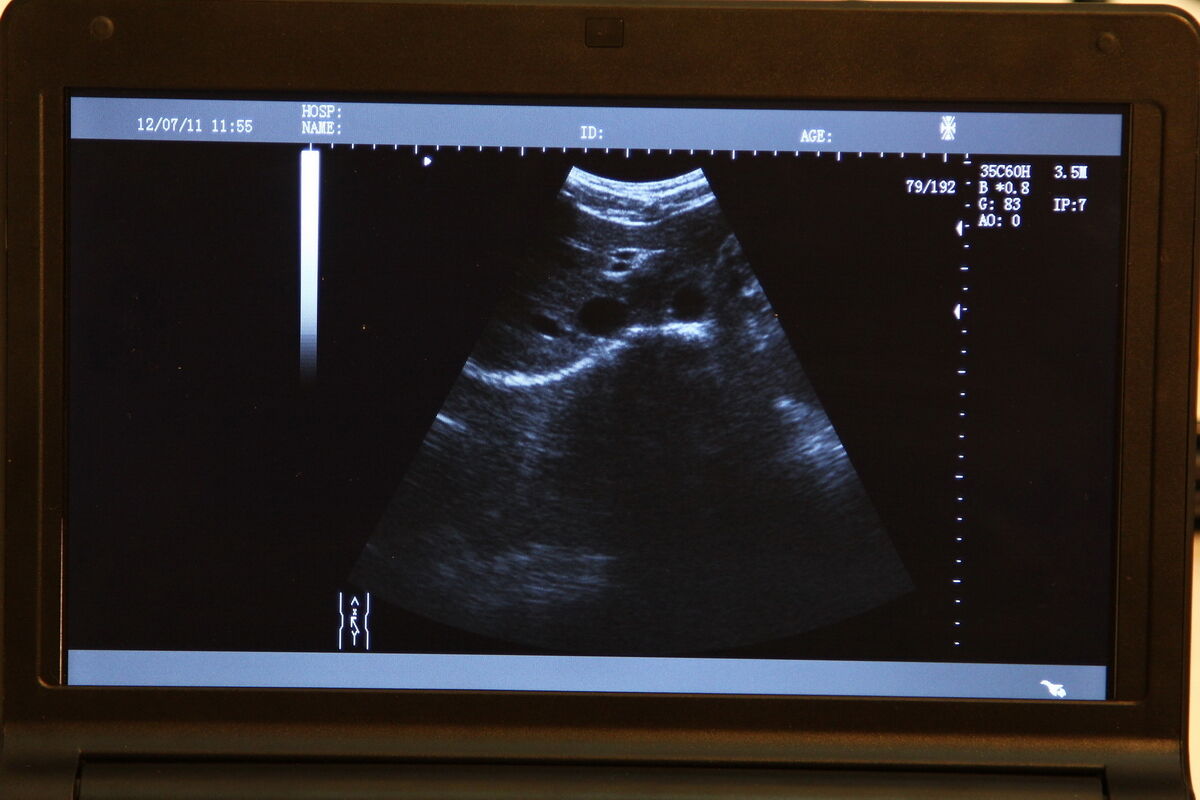

Healthcare professionals will appreciate the detailed imaging capabilities of this Medical Laptop Machine Ultrasound. The 7.5MHz linear transvaginal probe ensures clarity and precision, allowing for accurate diagnosis and treatment planning. The linear transvaginal probe is particularly useful in gynecology and obstetrics, because it provides clear images of the reproductive organs. Additionally, it can also be used for various other medical applications, including vascular and musculoskeletal examinations.

This ultrasound scanner is designed with the user in mind. It offers a clear and bright display, so images can be viewed in great detail. The touch-screen functionality ensures intuitive operation, making it easier for professionals to focus on patient care rather than struggling with complex machinery. Additionally, it comes with multiple connectivity options, so transferring data and images to other devices or systems is seamless and straightforward.